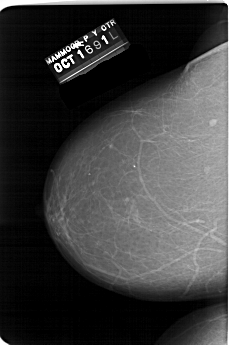

A_1542_1.LEFT_MLO

LEFT_MLO LINES 5821 PIXELS_PER_LINE 3901 BITS_PER_PIXEL 12 RESOLUTION 43.5 NON_OVERLAY